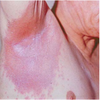

Psoriasis type?

Plaque